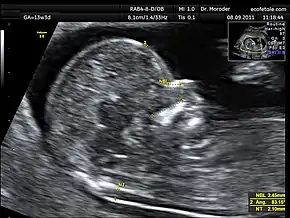

Measurements of fetal nuchal translucency, nasal bone and facial angle according to the standards of the Fetal Medicine Foundation

A nuchal scan or nuchal translucency (NT) scan/procedure is a sonographic prenatal screening scan (ultrasound) to detect chromosomal abnormalities in a fetus, though altered extracellular matrix composition and limited lymphatic drainage can also be detected.[1]

Nuchal scan (NT procedure) is performed between 11 and 14 weeks of gestation, because the accuracy is best in this period. The scan is obtained with the fetus in sagittal section and a neutral position of the fetal head (neither hyperflexed nor extended, either of which can influence the nuchal translucency thickness). The fetal image is enlarged to fill 75% of the screen, and the maximum thickness is measured, from leading edge to leading edge. It is important to distinguish the nuchal lucency from the underlying amniotic membrane.[8]